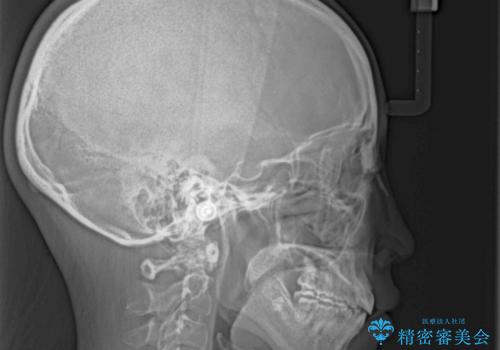

口が閉じられない ワイヤー装置による矯正治療

- 前歯が突出しているために口が閉じられないとのことで来院された患者様です。

上下ともに顎が小さく、歯列が前方に突き出していたため、上下左右の第一小臼歯4本を抜歯し、口元の突出感を改善していくこととしました。